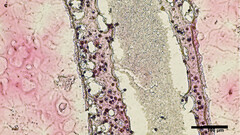

Gli scienziati della University of British Columbia (UBC) sono riusciti a stampare in 3D repliche di strutture tubolari produttrici di sperma fatte da cellule testicolari vitali. Il materiale per la biostampa è stato raccolto tramite biopsia delle cellule staminali testicolari di pazienti che hanno l'azoospermia non ostruttiva (NOA), la forma più pesante di infertilità maschile. Queste protocellule sono state poi coltivate e moltiplicate prima di essere stampate in 3D in una struttura tubolare simile a quella degli spermatozoi situati nei testicoli umani

Non solo il metodo di bioprinting ha avuto successo in termini di sopravvivenza delle cellule, ma dopo 12 giorni i tubi sono stati esaminati e il materiale "era maturato in molte delle cellule specializzate coinvolte nella produzione di sperma". Inoltre, i finti tubi testicolari "mostravano un miglioramento significativo nel mantenimento delle cellule staminali spermatogoniche - entrambi i primi segni di capacità di produrre sperma", dice il rapporto. Secondo il ricercatore principale dello studio, il dottor Ryan Flannigan, professore assistente di urologia dell'UBC:

L'obiettivo del team di ricerca è ora quello di sperimentare l'alimentazione delle cellule bio-stampate con vari nutrienti e fattori di crescita adeguati, al fine di indurle alla produzione di sperma vitale che potrebbe successivamente essere utilizzato in nuovi trattamenti di infertilità per le coppie che cercano di concepire.